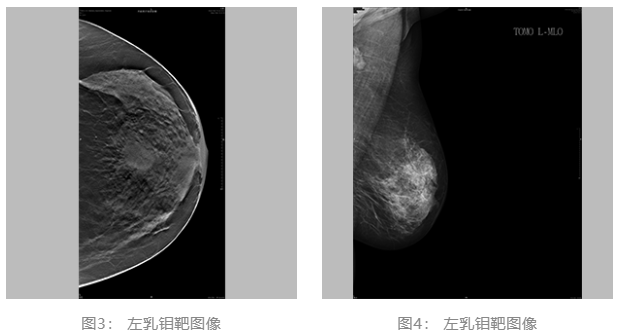

2021.06.30乳腺体层成像:双乳ACR c型。左乳肿块,BI-RADS 4C 类。双乳腺体增生样改变,BI-RADS 2类。(图3、4)

▌乳腺体层成像: